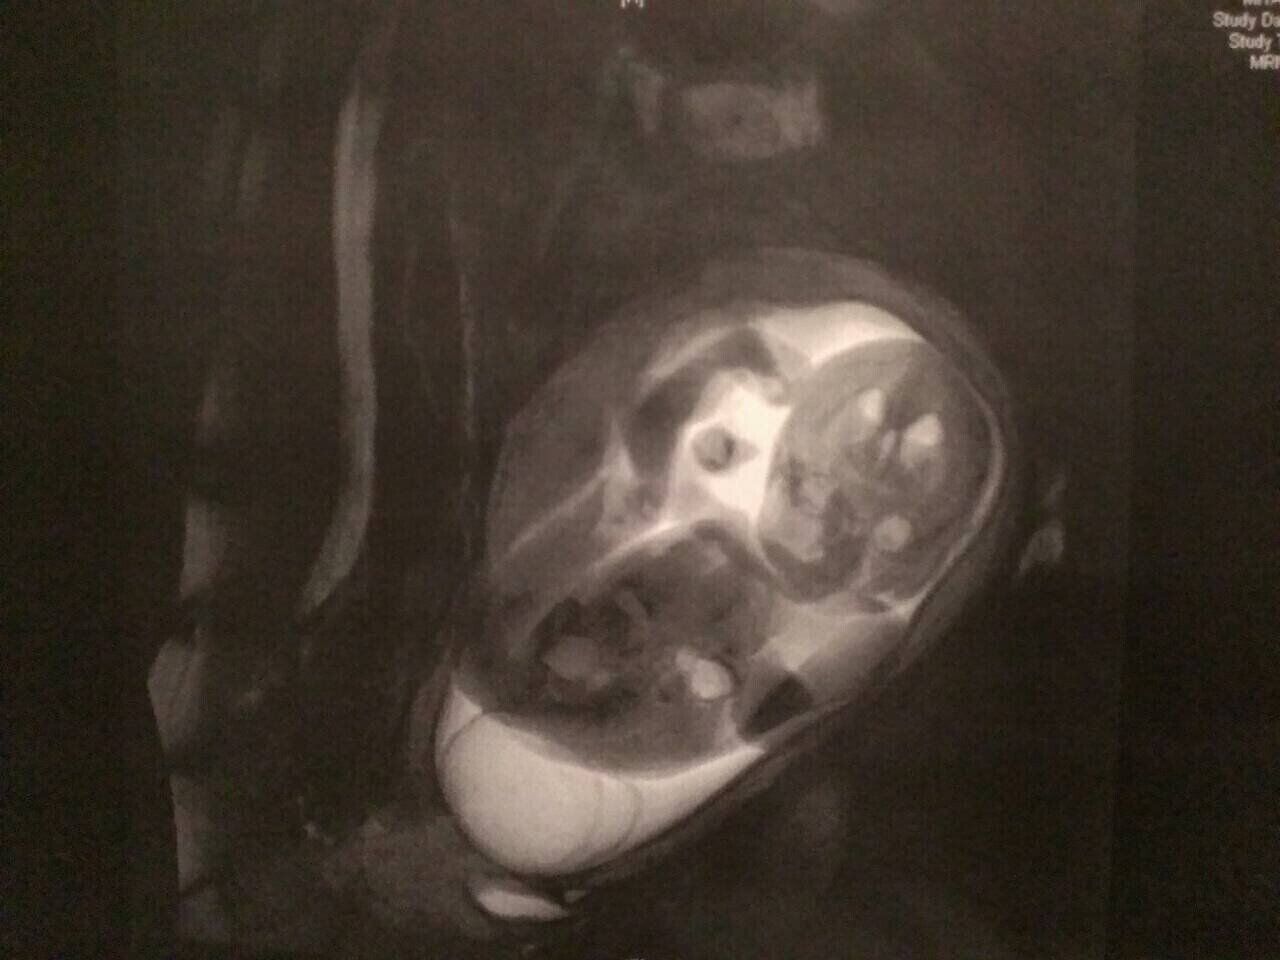

2月頭、妊娠7カ月(26週目)に国立成育医療研究センターを初受診。じっくりエコー検査をしたあと、今後のことについて説明を受け、2週間後の健診では胎児MRIを受けました。

「脊椎が開いている幹部は、比較的低い位置だとわかりました。低い位置ほど独立歩行の可能性が高まるそうなので、少しだけ希望が見えました。でも、排せつ障害や下肢まひによる歩行困難はあるそう。水頭症やキアリ奇形の可能性も消えていません。

「おしりのあたりのふくらみを、前回よりもさらに詳しく調べていました。心臓、そのほかの臓器、頭の中もじっくり見ているのがわかりました。その結果、二分脊椎と診断され、水頭症やキアリ奇形の可能性があることも告げられました」(香織さん)

水頭症は、脳と脊髄を覆う髄液が過剰にたまってしまい、脳室が拡大する病気。キアリ奇形は、本来は頭蓋骨の中にあるはずの小脳や脳幹の一部が、頭蓋骨の出口の穴(大孔)を通って、脊柱管内へ落ちこんでしまう病気です。